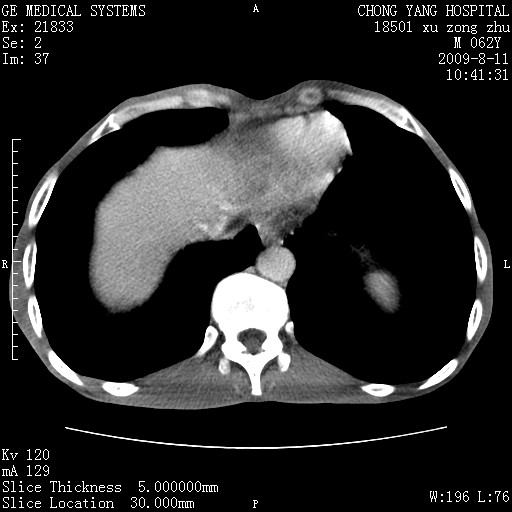

以下是引用杀毒软件在2009-8-11 16:35:00的发言:[br]肝内胆管扩张局限于左叶,胆管内有结石伴肝外胆管结石,胆管壁增厚呈弥漫性并发腹腔积液,胰腺边界模糊。[br][br]考虑---胆总管及肝内胆管结石继发胆管炎及胰腺炎,左肾下极囊肿,腹水。

以下是引用zjzjr在2009-8-11 17:35:00的发言:[br]肝内胆管扩张局限于左叶,胆管内有结石伴肝外胆管结石,胆管壁增厚呈弥漫性并发腹腔积液。[br][br]考虑---胆总管及肝内胆管结石继发胆管炎,左肾下极囊肿,腹水。